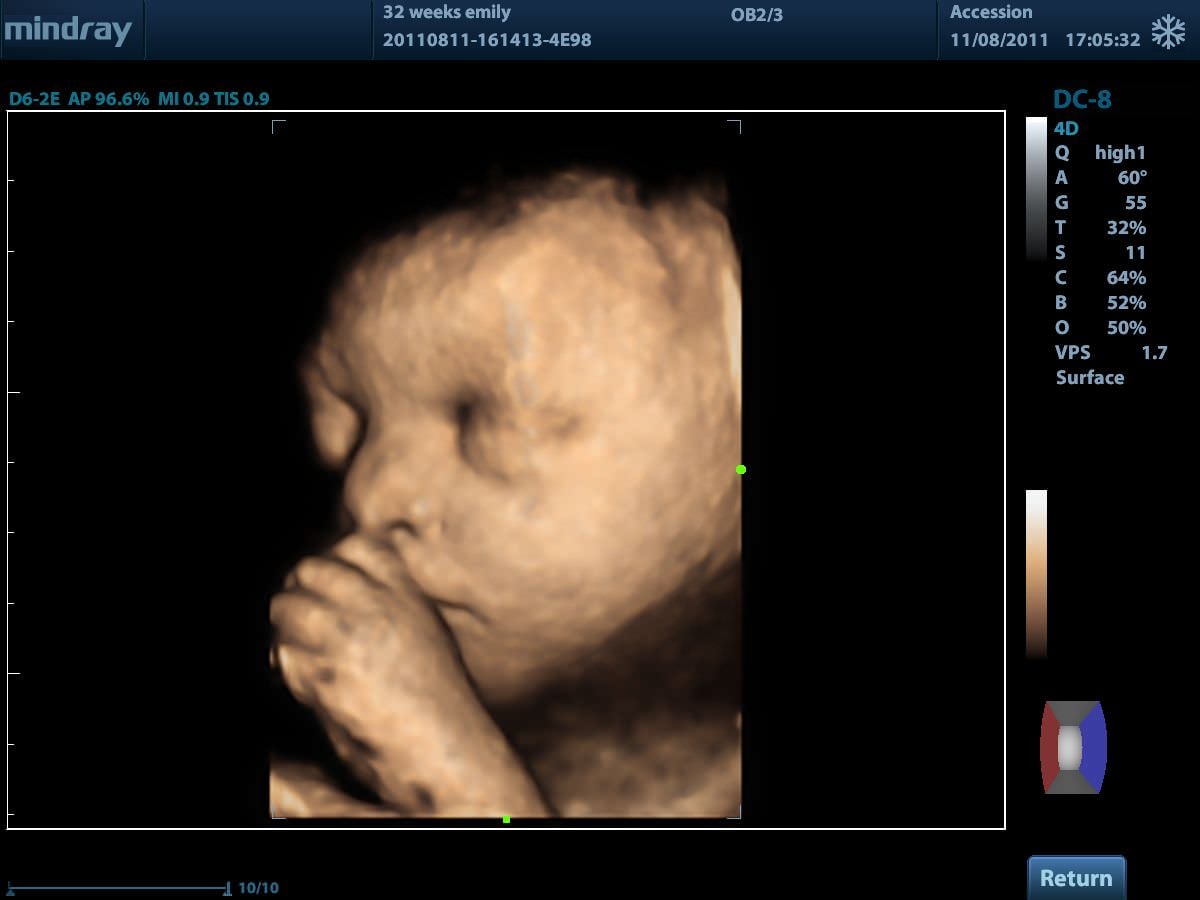

4D (трехмерное сканирование в реальном времени)

- 4D Module. 4D Модуль для подключения объемных датчиков

- Smart OB. Программа автоматического измерения основных параметров биометрии плода в акушерстве

- iLive. Режим построения объемного изображения с применением технологии виртуальной свето-теневой обратоки с возможностью перемещения источник